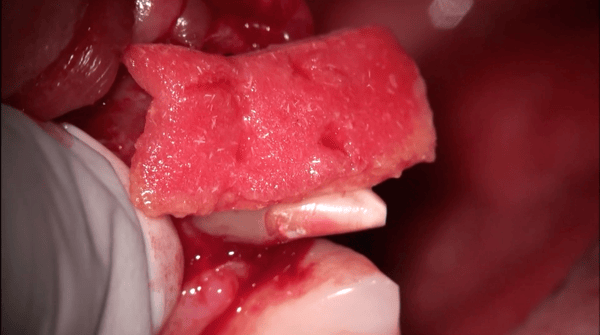

The OsteoGen Bone Grafting Strip infuses bone graft into a collagen strip to eliminate the problems associated with particulate migration. Unlike the Osteogen Plugs, which are generally used when all the socket walls are intact, the Osteogen Strips are perfect to repair a missing wall or defect.

- Flexible strips easily conform to the grafting site, eliminating gaps in bony walls

- Eliminates chance of particulate wash out; crystals are contained in the collagen

- Can be folded or layered to created added volume and packed into defect space

- Combines our OsteoGen ® Bioactive Resorbable Calcium Apatite with a bovine achilles tendon collagen matrix to create a structure that mimics the organic and inorganic components of physiologic bone.

- The Bovine Achilles Tendon collagen carries the bone graft for easy and efficient delivery to the site, eliminating the hassle and time spent mixing and packing particulate grafts while also eliminating the potential for graft wash out.

- The Type I collagen acts as a wound dressing not only to stabilize the clot, but also to absorb and deliver blood flow to the slowly resorbing graft, a feature critical for the initiation of bone formation and early angiogenesis.